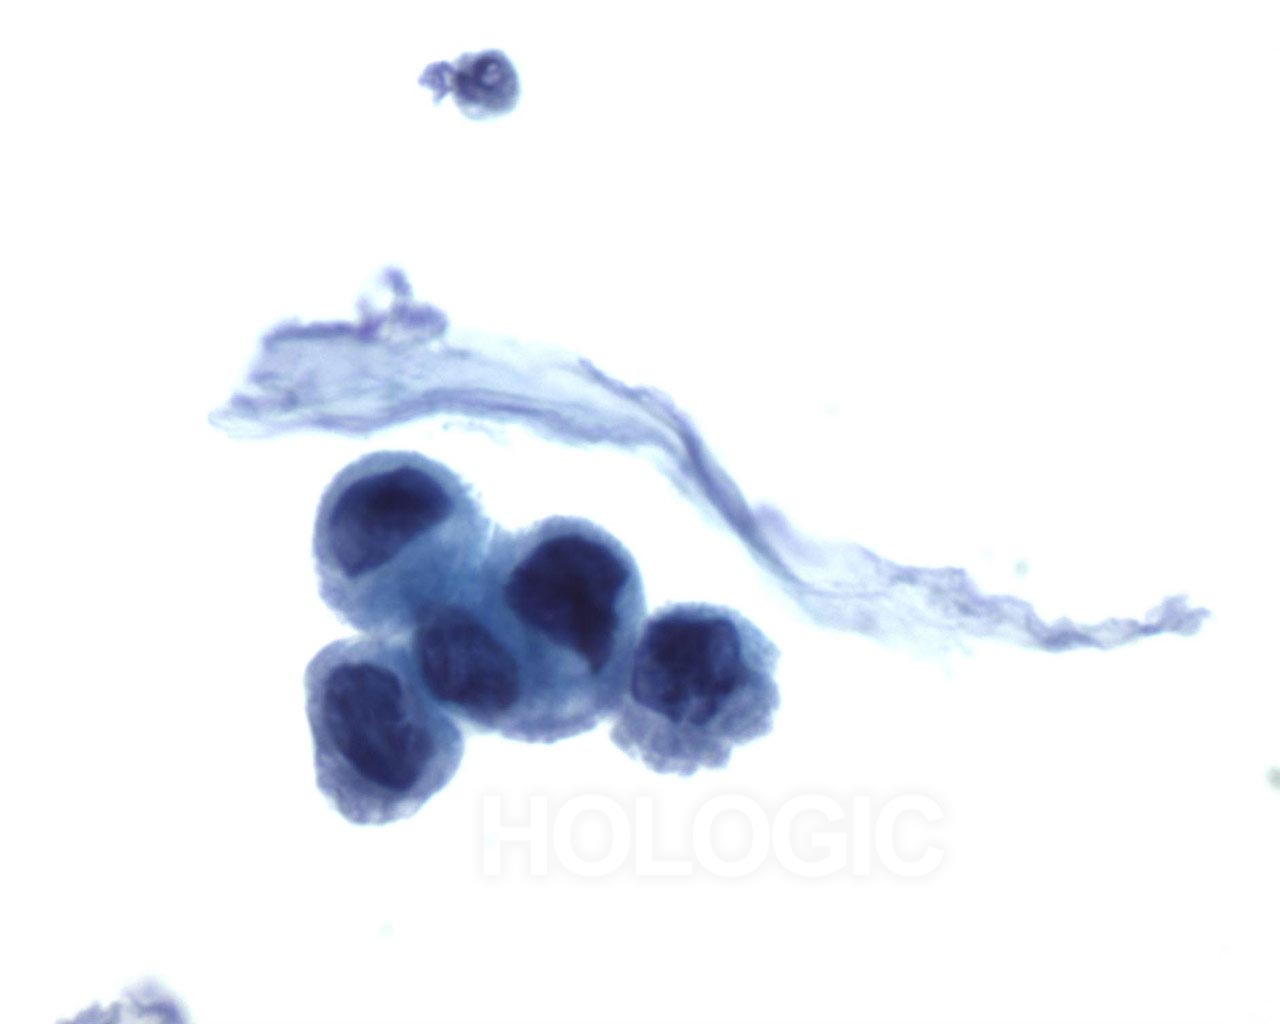

Urinary Tract Cytology - Low Grade Urothelial Carcinoma

LOW GRADE UROTHELIAL CARCINOMA AND CARCINOMA IN SITU